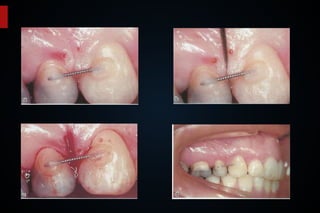

Migração patológica dos incisivos, perda do elemento 25, resultado mantido com retenção (L /V)

Não houve progressão do colapso dos tecidos periodontais.

Perda da papila entre os Incisivos, prolongamento da área de contato.